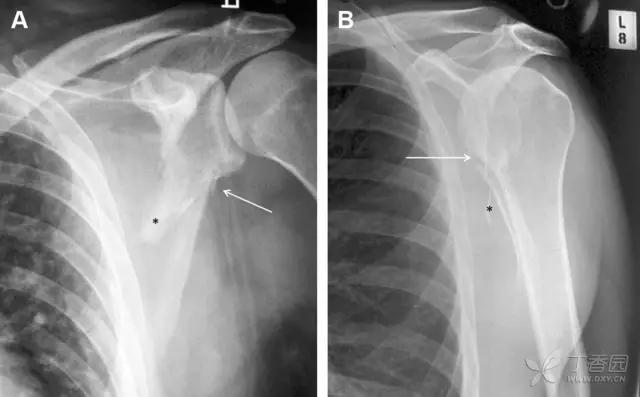

27 肩峰骨折

肩峰骨折为高能量损伤,多由直接*力暴**导致,好发于中青年患者,多伴有肩关节其它结构损伤。有必要拍摄 Rockwood 位(前后位片,X 线束尾倾),特别有利于显示肩峰下部及肩峰下间隙。

图 5 肩峰骨折。内旋位前后位(A)片上,骨折线几乎被喙突完全遮挡, 但是在标准前后位(B)和腋位(C)片上可见骨折线